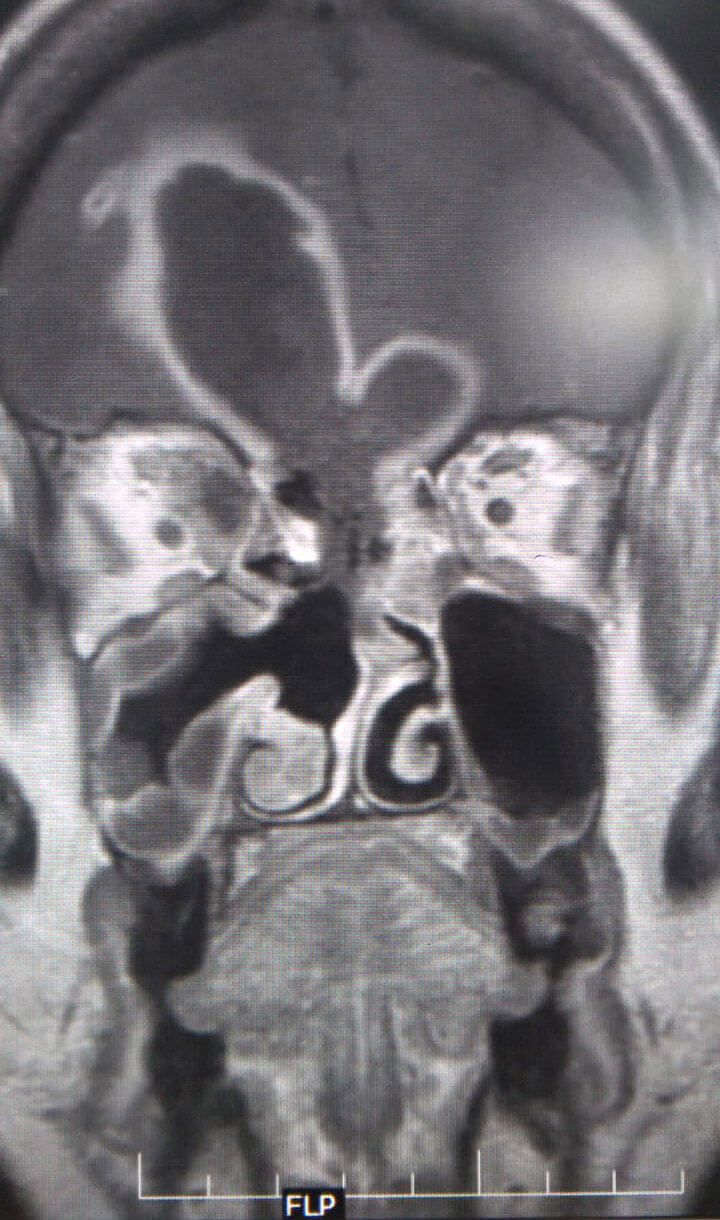

MRI scans of a patient with ROCM showing a large frontal lobe brain abscess

with necrosis of the cribriform plate (coronal and sagittal views).